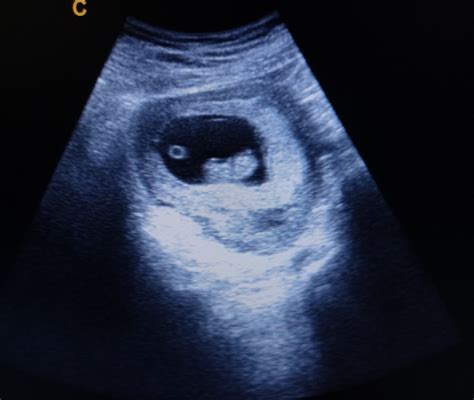

La camera gestazionale rappresenta il primissimo segno di gravidanza visibile all'ecografia. Si forma nell’utero materno subito dopo l’impianto dell’embrione e costituisce il nido all’interno del quale si svilupperà il bambino. La sua formazione è un processo naturale che segue l'annidamento dell'ovulo fecondato nella parete uterina. Nelle primissime settimane, prima ancora che l'embrione sia chiaramente distinguibile, all'interno della camera gestazionale è visibile il "sacco vitellino". Questa struttura, simile a una sorta di paracadute a cui è attaccato l'embrione, fornisce alle prime cellule i nutrienti essenziali per le prime fasi di sviluppo.

La camera gestazionale è delimitata dalla membrana amniotica, che, grazie alla presenza del liquido amniotico, protegge il piccolo dalla forza di gravità e da eventuali traumi. Dal punto di vista ecografico, la camera gestazionale è inizialmente una sacca contenente liquido amniotico, che appare come un'area scura (nera) nelle immagini.

- Verso le 4 settimane: Si osserva la camera gestazionale, che è lo spazio in cui l'embrione crescerà.

- Verso le 5/6 settimane: Si può iniziare a vedere l'embrione, soprattutto se ha raggiunto i 5 mm. È anche possibile osservare le prime attività cardiache.

- Tra le 6 e le 8 settimane: L'attività cardiaca embrionale, il cosiddetto "sfarfallio", diventa più evidente e facilmente riconoscibile.

Le misurazioni della camera gestazionale e la sua evoluzione sono valutate insieme all'epoca di amenorrea (il mancato arrivo delle mestruazioni). Tuttavia, è possibile che l'epoca gestazionale calcolata non sia corretta, dunque è normale riscontrare misurazioni più piccole rispetto al previsto. Per questo, ciò che bisogna valutare è l'evoluzione della misurazione a distanza di una settimana. Quando si rileva una camera gestazionale che misura circa 25 mm, ci si aspetta di vedere anche l'embrione al suo interno.

La circostanza in cui si osserva una camera gestazionale senza la presenza di un embrione visibile (e senza sacco vitellino) è definita "camera gestazionale vuota" o, in un contesto più ampio, "gravidanza anembrionica". Questo significa che lo sviluppo embrionale si è interrotto prima che l'embrione fosse rilevabile o che non si sia mai formato.